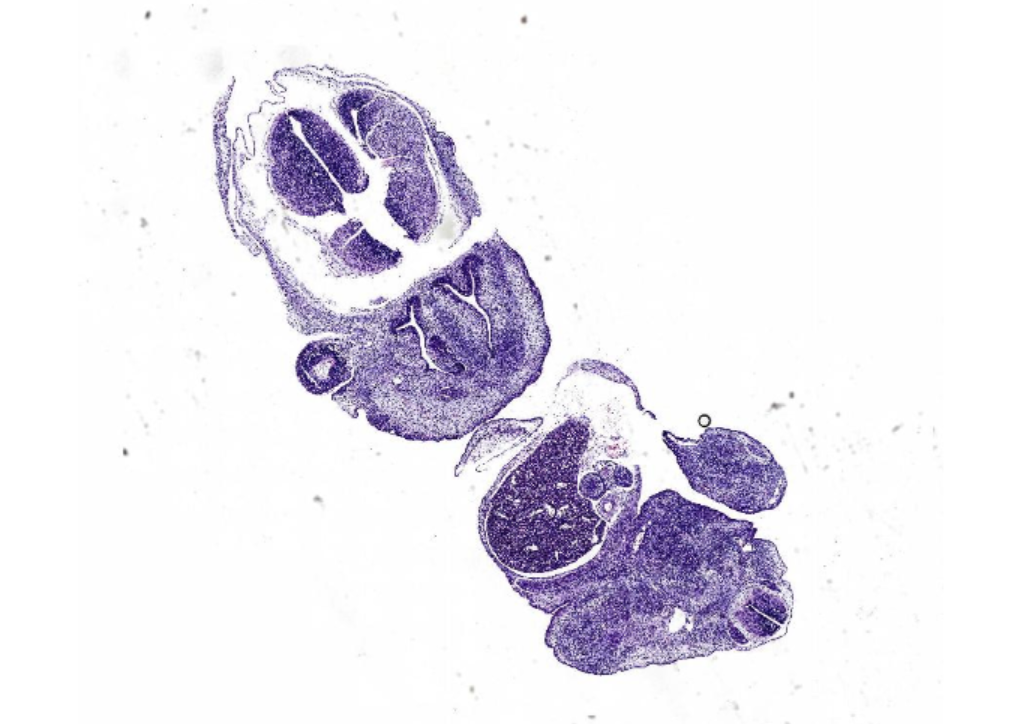

| 芯片编号: | XN480001 | ||||||||||||||

| 芯片名称: | 多器官正常组织组合芯片,24例/48点 | ||||||||||||||

| 芯片说明: | 多器官正常组织组合微阵列,包含12种器官(大脑、心脏、肺、肝、 宫颈、结肠、肾、乳腺、卵巢、胰腺、前列腺和皮肤),每种器官取两例。 |

||||||||||||||

| 取样方式: | 一例两点 | ||||||||||||||

| 点数: | 48 | ||||||||||||||

| 例数: | 24 | ||||||||||||||

| 点样直径: | 1.5mm | ||||||||||||||

| H&E染色片库存: | 20 | ||||||||||||||

| 组织固定方式: | 福尔马林固定24h | ||||||||||||||

| QA/QC: | HE染色和IHC染色 | ||||||||||||||